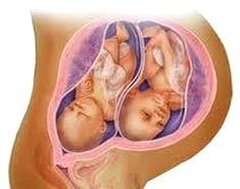

Багатоплідна вагітність причини особливості

Народження двійнят, а тим більше, троє чи більше близнюків, - справа хвилююча, радісне, щасливе. Але і турбот, клопоту майбутнім батькам доведеться помітно більше.

І починаються складності ще до появи маляток на світло, в період виношування. У чому ж особливості багатоплідної вагітності, зараз і будемо з'ясовувати.

Чому одні двійнята мало схожі один на одного, а інші - майже як «клони»? Чи є відмінності в їх походження? Виявляється, такі існують, фахівці розрізняють монозиготних близнюків, простіше їх називають однояйцевими, і дизиготних (двуяйцевих), трапляється і многояйцевих вагітність. Трійні і четверняшкі можуть з'являтися на світло в різних комбінаціях однояйцевих і многояйцевих, але відстежувати таку рідкісну багатоплідної вагітність по тижнях - не мета даної статті. Тут докладніше поговоримо саме про двійнята.

Монозиготні (однояйцеві) двійнята мають однаковий набір хромосом, оскільки зачаті в одній яйцеклітині, яка потім поділяється на два зародка. Це саме близнюки, вони схожі один на одного так, що стороннім важко розрізнити.

У дизиготних двійнят хромосомні набори трохи відрізняються, це обумовлено особливостями запліднення: розвиваються ці зародки з різних яйцеклітин, і їх схожість набагато менше.